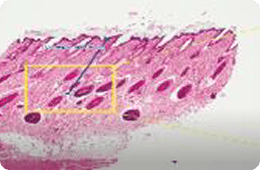

1064 PS

침투깊이 : 499.98~935.23 μm

침투깊이 : 257.12~287.38 μm

출처 : Effect of fractional picosecond laser therapy using a diffractive optical lens on histological tissue reaction, Journal of cosmetic and laser therapy, 2024